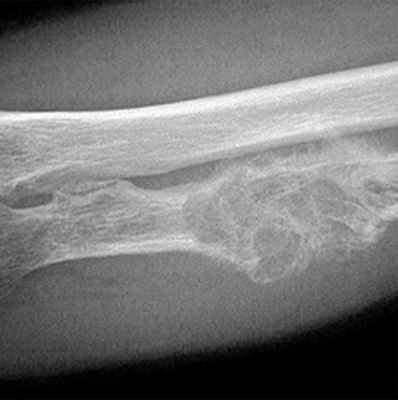

- Деструкция с «разъеданием» костной структуры на рентгенограммах выглядит как дефект – «дырка», такой вариант метастазирования называют остеолитическим, что буквально означает «съеденная кость».

- При утолщении кости за счёт опухоли рентгенограмма выявляет «плюс ткань», тогда говорят об остеопластическом метастазировании.

- Как правило, у больного встречаются оба вида метастазов с превалированием одного из вариантов, в большинстве случаев остеолитического.

У пациентов с переломами, особенно у пожилых людей, важно определить, является ли данный перелом патологическим по причине заболевания раком. Можно заподозрить такой перелом, особенно если у пациента диагностирован первичный рак. Однако перелом может быть первым проявлением рака в другом месте тела. Рентгенографическое изображение может иметь деструктивный характер, что предполагает наличие рака, но может иметь только незначительные аномалии, например, такие как точечные кальцификации, которые легко пропустить и которые могут быть единственными признаками, указывающими на наличие опухоли. Кроме того, хотя это и нетипично, поражение кости, которое считается причиной метастатического перелома, может быть переломом, вызванным первичной опухолью кости, такой как хондросаркома или остеосаркома. Дифференциацию атипичного (возраст пациента или рентгенологический признак) деструктивного «метастатического» поражения с переломом или без него, особенно с наличием точечных кальцификаций, от редкой первичной опухоли кости следует проводить вместе с онкологом или рентгенологом, специализирующемся на мышечно-скелетных патологиях.